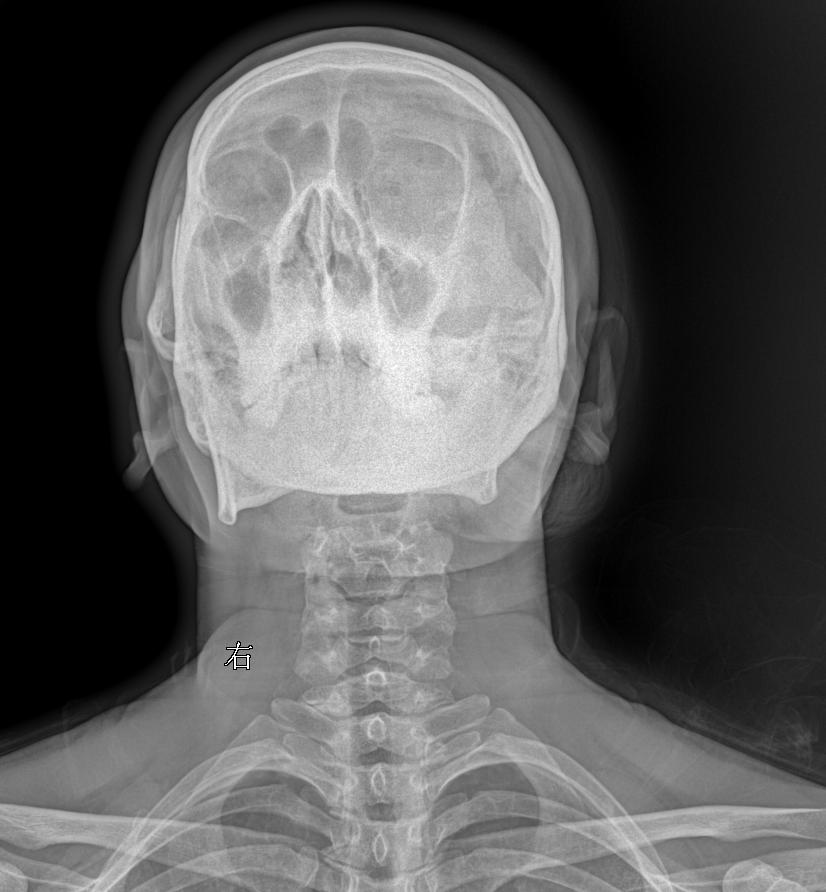

颈椎术后,疼痛就诊 45岁